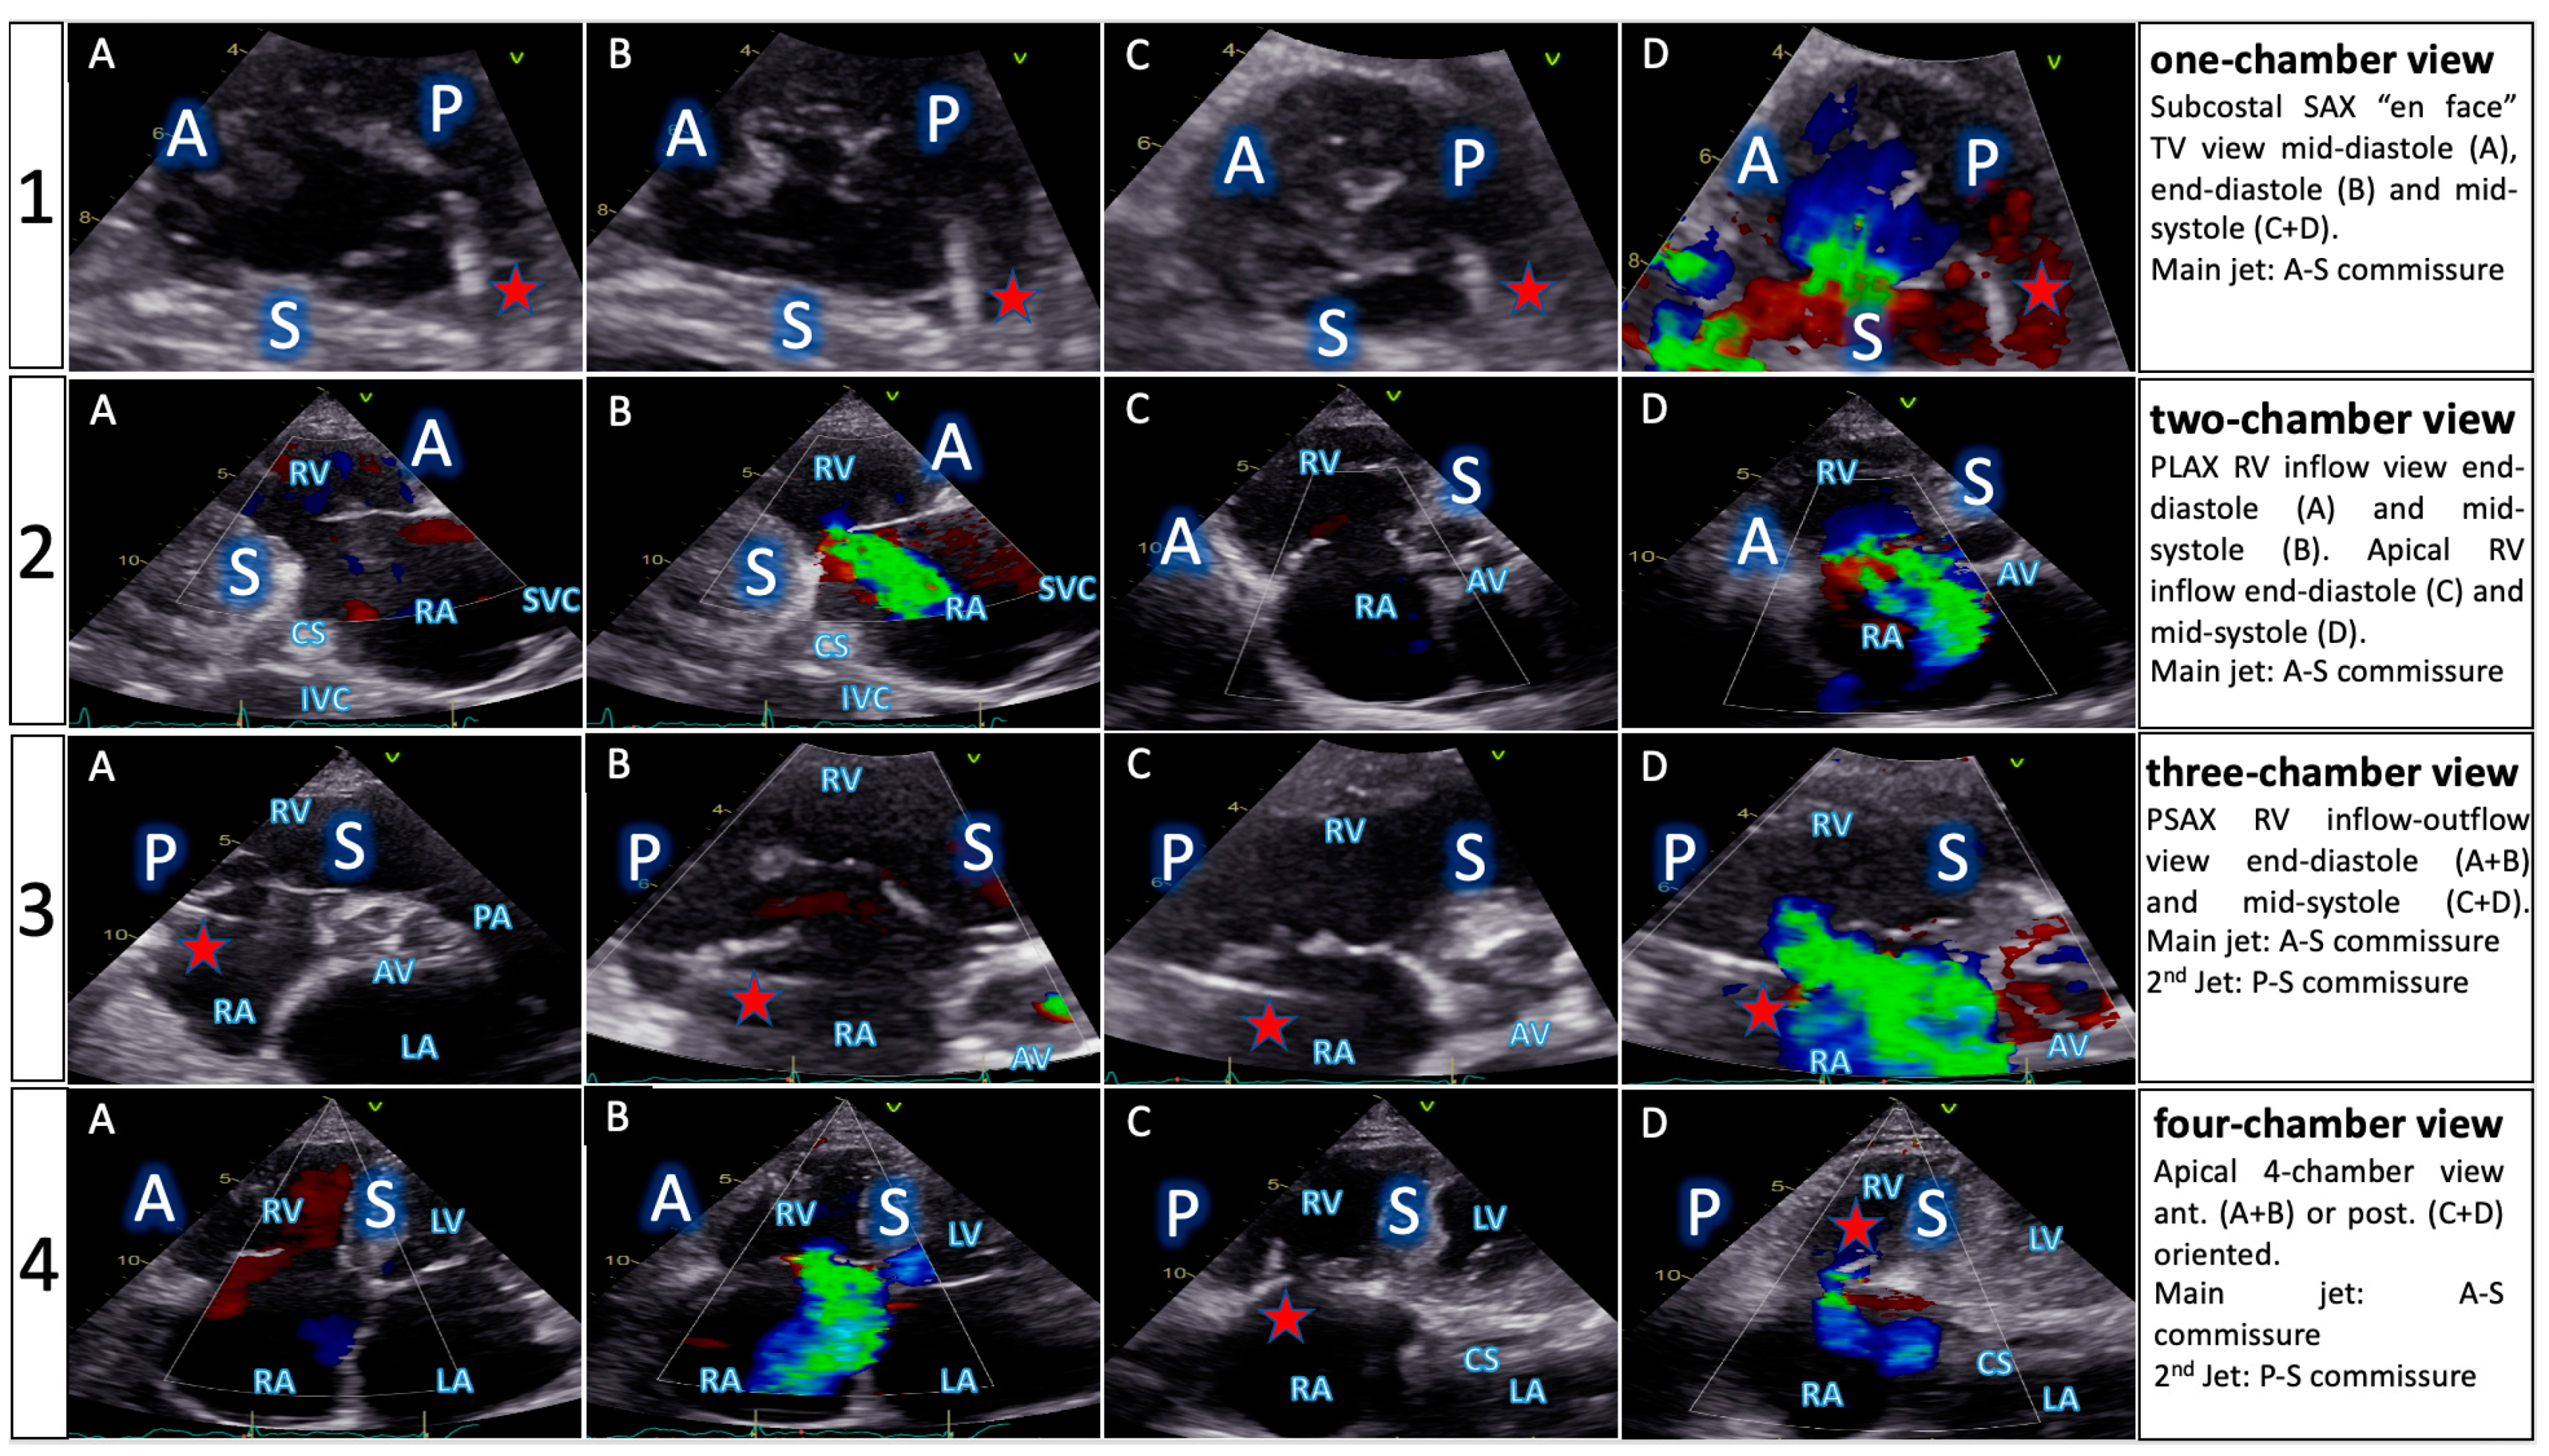

| TTE View | Focus | ||

|---|---|---|---|

| Functional Parameters | Right Heart Morphology | TV Anatomy | |

| PLA standard | LVOT diameter (Qs/CO calculation) | RV function and size (eyeballing) | -- |

| PLA RV inflow RH two-chamber view | TR severity (eyeballing) TR Jet VC and PISA (optional) | RV function and size (eyeballing) | AL visualization SL vs. PL distinction |

| PSA standard RH three-chamber view | TR severity (eyeballing) RVOT VTI RVOT diameter | RV size PA size | Leaflet distinction, if possible |

| PSA-modified alternative RH one-chamber view | TR severity (eyeballing) | TV annulus size Coaptation gap | Simultaneous visualization of all leaflets |

| A4C RH four-chamber view | TR Jet area, VC and PISA TR VTI, RVSP TAPSE RV free wall TDI RV FAC RA volume RV diameters LVOT VTI (A5C/A3C) | RV function and size RA size TV annulus size Tenting height | SL visualization AL vs. PL distinction |

| A2C right alternative RH two-chamber view | TR Jet area, VC and PISA | RA size TV annulus size | AL visualization |

| Subcostal long axis | Hepatic systolic vein flow reversal Inferior vena cava size | RV function and size (eyeballing) | PL visualization AL vs. SL distinction |

| Subcostal short axis RH one-chamber view | TR severity (eyeballing) | Coaptation gap | Simultaneous visualization of all leaflets |